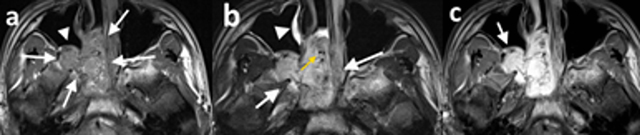

Figure 3

15-year-old male patient (patient 1), (a) axial T1-weighted precontrast, (b) axial T2-weighted precontrast, and (c) axial T1-weighted postcontrast MR images demonstrate a right-sided nasopharyngeal mass which enlarges the ipsilateral pterygopalatine fossa (a and b white arrows). The mass is isointense with the muscle on T1-weighted image (a) and hyperintense on T2-weighted image (b) and exhibits significant contrast enhancement (c). The posterior wall of the maxillary sinus demonstrates anterior bowing with resultant Holmann Miller sign (a, white arrowhead; c, arrow). The tumor demonstrates signal-void regions (b, yellow arrow) and inflammatory signal changes in maxillary sinuses (b, white arrowhead).

JNA is a histopathologically benign tumor, but it extends into adjacent foramina, fissures, and sinonasal spaces and demonstrates a locally invasive behaviour [114]. Although it may extend into unexpected locations, it usually follows a predictable spread pattern. Originating from the sphenopalatine foramen, the pterygoid process, and the sphenoid sinus, JNA mostly extends medially and laterally, largely because it encounters less resistant barriers in these directions [6]. Medially, the tumor usually invades the nasopharynx, the nasal cavity, and the maxillary and ethmoid sinuses. Laterally, it invades the pterygopalatine fossa and causes an anterior bowing of the posterior wall of the maxillary sinüs (Holmann-Miller sign) (Figure 3). Through the pterygomaxillary fissure, the tumor extends into the infratemporal fossa and laterally into the cheek [16].

The expansion of the pterygopalatine fossa due to the presence of a nasopharygeal mass causes anterior bowing of the posterior wall of the maxillary sinus, and this sign (the antral sign or Holmann-Miller sign) is one of the characteristic findings of JNA [617]. Three out of six patients in this study exhibited Holmann-Miller sign, and the pterygopalatine fossa was expanded in all of our cases.